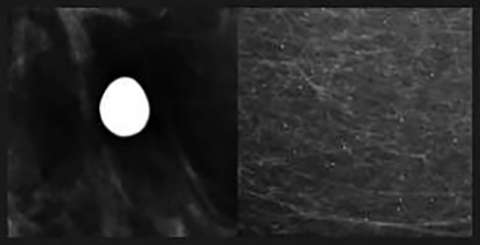

Rim Calcifications

Rim Calcifications: Include the previously described “eggshell” and “radiolucent centered” calcifications. These correspond to calcifications along round lesions such as oil cysts or simple cysts. These are usually associated with history of trauma or surgery.